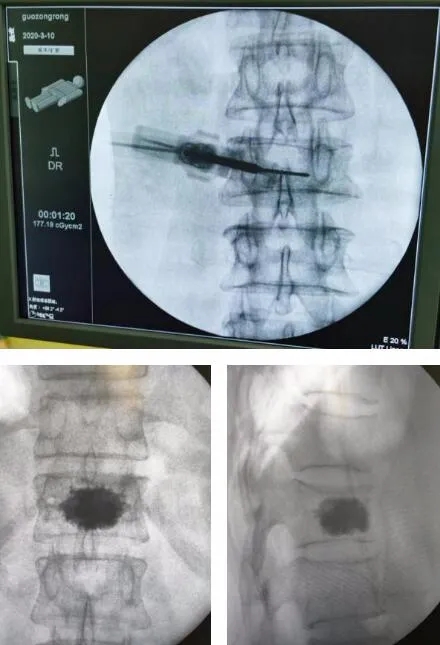

Ó뻼Õß¼°¼ÒÈ˾ÙÐÐÏàͬºó£¬£¬£¬£¬£¬£¬£¬£¬Ë¼Á¿µ½»¼ÕßÒÑ76Ëê¸ßÁ䣬£¬£¬£¬£¬£¬£¬£¬×Ô¼º»¼ÓÐÑü×µ¼äÅÌÍ»³ö£¬£¬£¬£¬£¬£¬£¬£¬Ñü×µÍËÐÐÐԸı䣬£¬£¬£¬£¬£¬£¬£¬»¹»¼ÓÐÍíÄêÈ˵ÄһЩ»ù´¡²¡£¡£¡£¡£¡£¬£¬£¬£¬£¬£¬£¬£¬ÊÖÊõΣº¦½Ï´ó£¬£¬£¬£¬£¬£¬£¬£¬ÕÅÒ±Ò½ÍâÐÐÊõÍŶÓÍŽáÄÚ¿Æ¡¢Âé×í¿ÆÕö¿ªÊõǰÌÖÂÛ£¬£¬£¬£¬£¬£¬£¬£¬ÉóÉ÷ÆÀ¹ÀÊÖÊõÇå¾²£¬£¬£¬£¬£¬£¬£¬£¬È·¶¨Ê¹ÓÃÌìçá?¹Ç¿ÆÊÖÊõ»úеÈ˾ÙÐÐ×µÌå³ÉÐÎÊõµÄÊÖÊõ¼Æ»®£¬£¬£¬£¬£¬£¬£¬£¬²¢Öƶ©×îÓÅ»¯ÊÖÊõ°ì·¨£¬£¬£¬£¬£¬£¬£¬£¬È·¶¨ÁËÊõÖÐËõ¶ÌÊÖÊõʱ¼ä£¬£¬£¬£¬£¬£¬£¬£¬³ä·Ö¸´Î»£¬£¬£¬£¬£¬£¬£¬£¬Ô¤·À¹ÇË®ÄàÉøÂ©±¬·¢£¬£¬£¬£¬£¬£¬£¬£¬ÊõºóÔ¤·ÀѬȾµÈһϵÁв½·¥¡£¡£¡£¡£¡£6ÔÂ22ÈÕ£¬£¬£¬£¬£¬£¬£¬£¬ÃÏ´óÒ¯µÄ×µÌå³ÉÐÎÊÖÊõ¾ÙÐС£¡£¡£¡£¡£ÊÖÊõÒ½ÉúÏÈ×°ÖÃ3Dµ¼º½»úеÈËʾ×ÙÆ÷£¬£¬£¬£¬£¬£¬£¬£¬Í¸ÊÓ¶¨Î»ÐØ12×µÌ壬£¬£¬£¬£¬£¬£¬£¬ÐÐ3D³ÉÏñ£¬£¬£¬£¬£¬£¬£¬£¬Ä£ÄâÐØ12×ó²à×µ¹¸ù´©´Ì£¬£¬£¬£¬£¬£¬£¬£¬ÔÚ¶¨Î»µã×öÒ»³¤Ô¼0.5ÀåÃ×Çпڣ¬£¬£¬£¬£¬£¬£¬£¬Í¨¹ýµ¼º½»úеÈËÌ×ͲÓÚÐØ12×ó²à×µ¹´òÈëµ¼Õ룬£¬£¬£¬£¬£¬£¬£¬Ö±ÖÁµÖ´ï×µÌåºó1/4´¦£¬£¬£¬£¬£¬£¬£¬£¬Ìæ»»¹ÇË®ÄàÊÂÇéÌ׹ܣ¬£¬£¬£¬£¬£¬£¬£¬Í¨¹ýÖÃÈëµÄ¹ÇË®Äà×¢ÈëÆ÷ÔÚ͸ÊÓÏ»ºÂý×¢ÈëÌî³äÔ¼2ml¹ÇË®Ä࣬£¬£¬£¬£¬£¬£¬£¬´ýÆðÔ´Äý¹ÌºóÔÙ´Î×¢Èë2ml¹ÇË®Ä࣬£¬£¬£¬£¬£¬£¬£¬È·¶¨×µÌå¸ß¶È»Ö¸´ÇÒÎÞÏÔ׏ÇË®ÄàÍâÒ磬£¬£¬£¬£¬£¬£¬£¬×îºóÈ¡³ö¹ÇÌî³ä×°Öᣡ£¡£¡£¡£ÊÖÊõ²»µ½1Сʱ˳Ë쿢ʡ£¡£¡£¡£¡£6ÔÂ24ÈÕ£¬£¬£¬£¬£¬£¬£¬£¬ÊõºóÁ½Ì죬£¬£¬£¬£¬£¬£¬£¬»Ö¸´ÓÅÒìµÄÃÏ´óÒ¯×øÔÚ´²±ßÁÏÀí£¬£¬£¬£¬£¬£¬£¬£¬×¼±¸³öÔº»Ø¼ÒÁË¡£¡£¡£¡£¡£